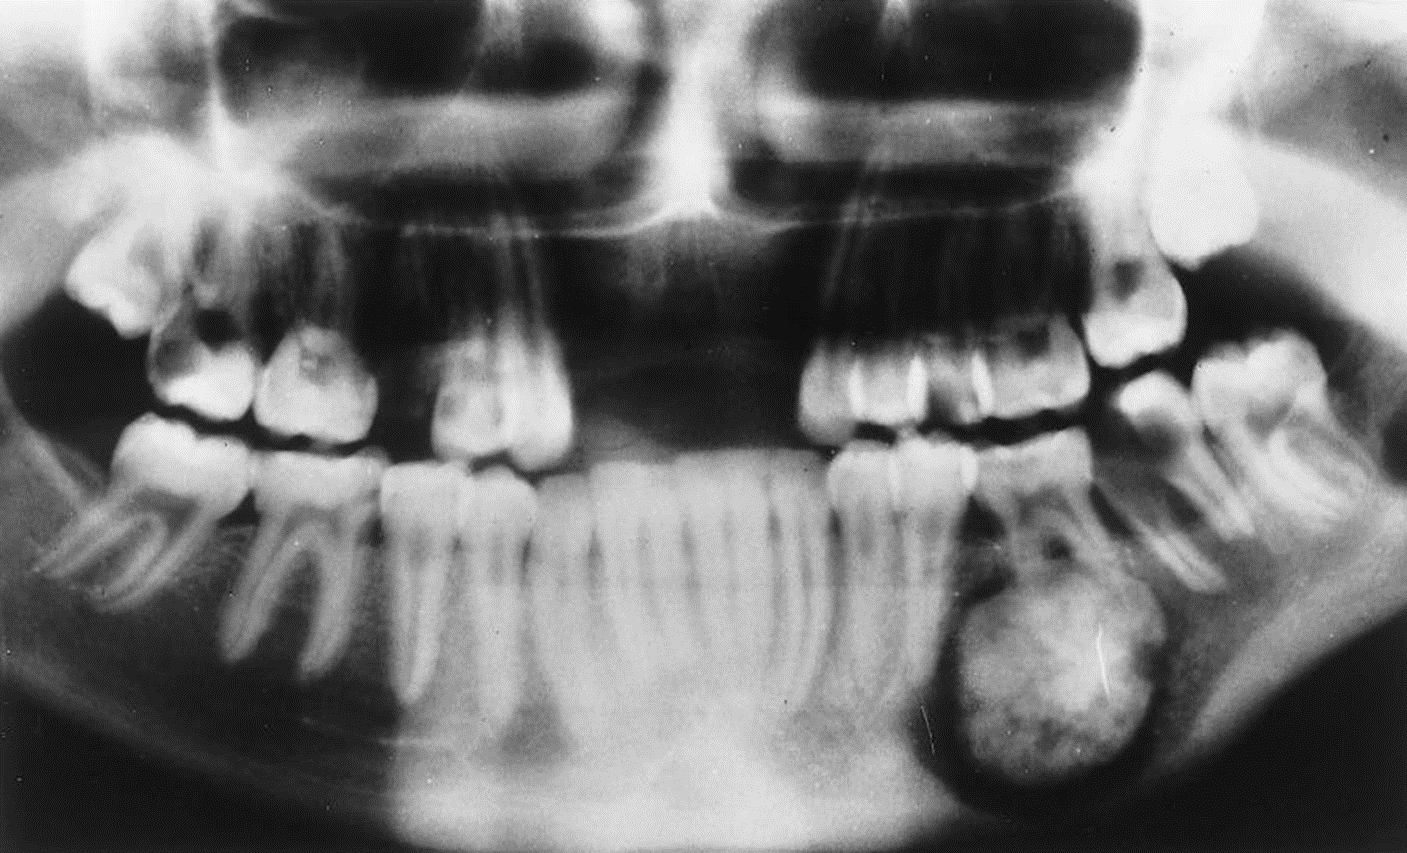

4. This 72-year-old woman presented with loose 20-yearold dentures and slight intermittent pain under the lower denture. She stated she had her teeth extracted because of severe untreated caries and abscessed teeth. The radiolucent lesion was detected on a radiograph of the painful area.

What is your diagnostic impression?